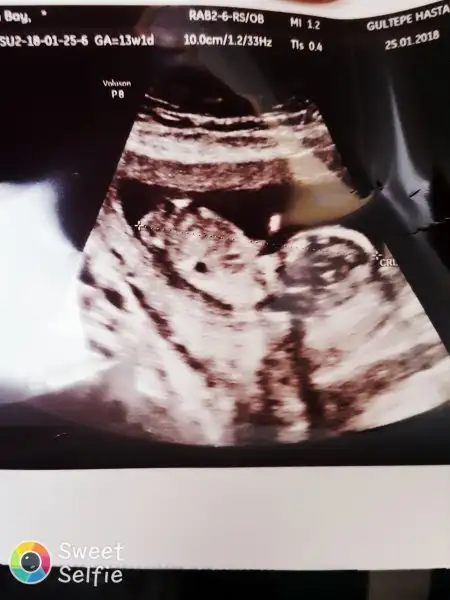

oylesine gttigim pimpirikli anne modumda kontrolden geldik cok sukur pasam iyi :) bagdas kurmus aga gbi oturuyormus :) devlet hastanesinin en buyuk kotulugu berbat bir ultrason fotografi ve bana gosterilmeyen bebek

Ayyyy burda fotoğraf bile vermiyorlar devlette ama doktor ekranı kendisi çevirip gösteriyor sağolsun. ehh buna şükür diyorum bende.